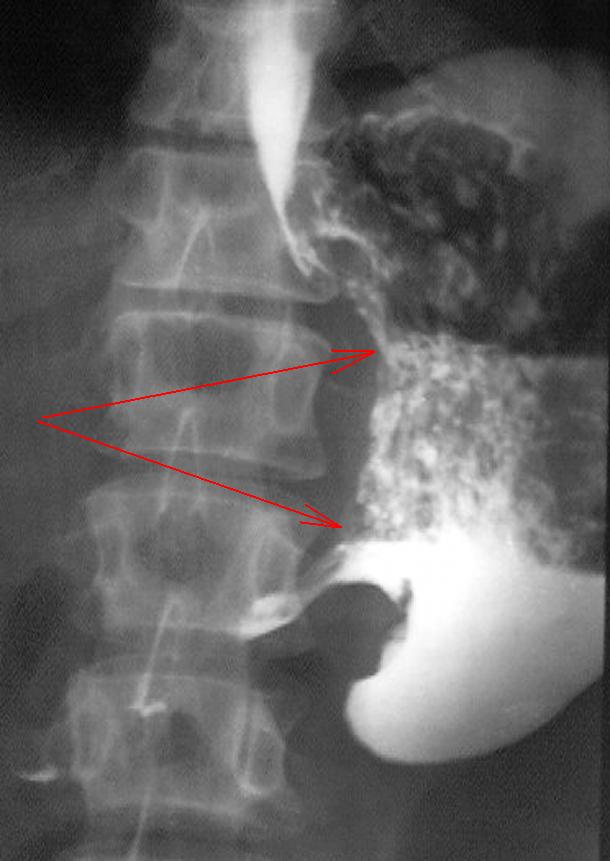

Скидываю сканы КТ-органов брюшной полости, сразу отмечаю, что специальная матодика для отценки стенок желудка не проводилась но на фоне рентген-контрастного вещества отмечается утолщение стенок антрального отдела желудка;

Протяженность процесса - как стрелки или более. О пилоростенозе какой ст.думаете?

Уважаемый Валентин Львович, мои старшие коллеги с опытом работы тоже самое мне предложили в проведении диф.диагностики. буквально на следующий день после проведения было сделано целенаправленное взятие биопсии где наши патоморфологи подтвердили, а еще через пару дней с целью исключения метастазов при проведении КТ-органов брюшной полости видно было четко на сканах мягко-тканный компонент опухоли желудка, сканы с вашего разрешения предоставлю завтра.

Красными стрелочками отмечено наличие мягко-тканного компонента инфильтративного роста.